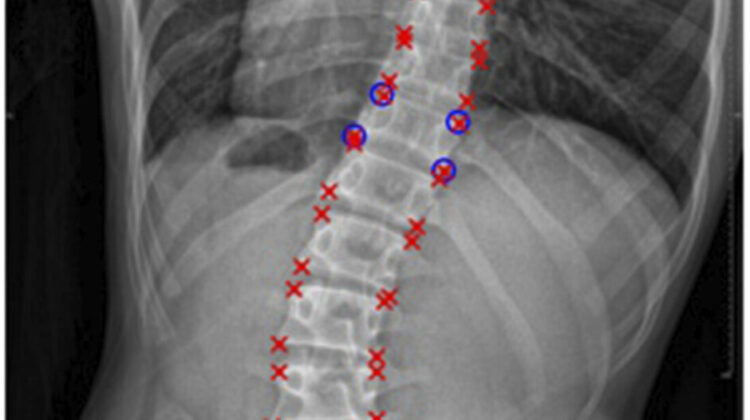

أهمية التشخيص المبكر لاعوجاج العمود الفقري وحداب شويرمان

التشخيص المبكر يلعب دورًا حيويًا في حماية الطفل من تفاقم الانحناءات. عند ملاحظة أي تغير في استقامة ظهر الطفل، أو شك الطبيب بوجود حداب شويرمان، يُنصح بإجراء فحص إشعاعي دقيق يشمل:

تحديد نوع الانحناء وموقعه.

قياس شدة الانحناء بدقة.

وضع خطة علاجية مناسبة قبل تفاقم الحالة.

هذا الفحص يساعد الطبيب على معرفة إذا كان هناك اعوجاج جانبي مصاحب للحداب، وهو أمر أساسي لتحديد العلاج الأمثل.